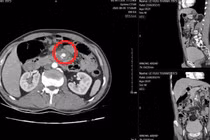

Thấy bất thường, chị T. quyết định tìm lên một bệnh viện tuyến trên để điều trị. Tại đây, chị được chụp MRI sọ não, phát hiện u tuyến yên (đường kính 3mm) và nghĩ đến u tuyến yên tiết TSH nên chị được chỉ định phẫu thuật theo hướng này.

Lo sợ khi phải động chạm đến dao kéo, chị T. quyết định đi khám ở Bệnh viện Nội tiết Trung ương để khẳng định chắc chắn tình trạng bệnh của mình trước khi phẫu thuật.